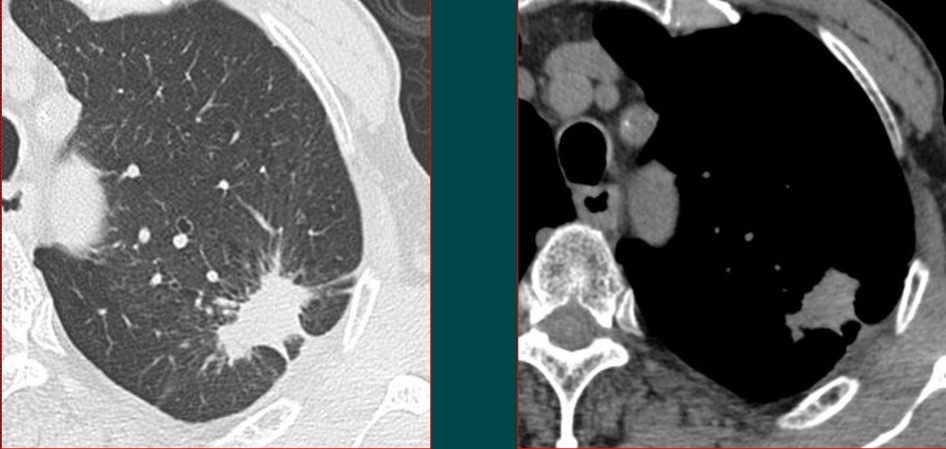

一般来说,发现了肺部小病灶,首先都要做一个胸部螺旋CT,如果是实性结节,可能还需要增强扫描观察病灶的血供特点,鉴别炎症、结核球和肿瘤。

胸部CT配合增强扫描,加上肿瘤标志物检测等临床资料,可以明确大部分恶性肿瘤。

这个病例是豪大夫的师傅,山东肿瘤医院的黄教授提供

这位病人是一位78岁的老爷子,体检发现左肺不规则结节,有毛刺,有胸膜牵拉,高度怀疑肺癌。

但是增强扫描发现病灶没有任何强化,说明病灶没有供血血管,提示这是一个结核球(结核杆菌会破坏一切,形成局部干酪样坏死,没有血管所以增强扫描不强化;少数活动期病灶可以周边包膜样强化;极少数明显均匀强化)。

后来进一步穿刺证实为结核性肉芽肿,避免了挨一刀。